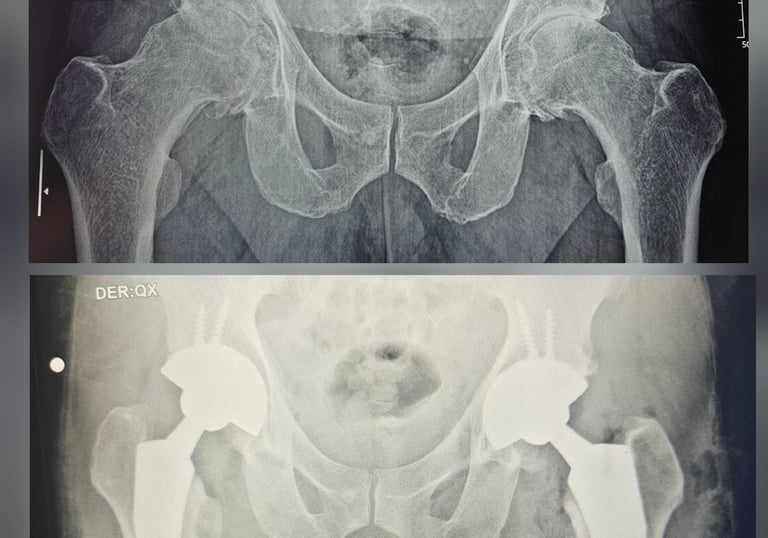

Cirugía Articular

Realizamos procedimientos quirúrgicos avanzados para mejorar la calidad de vida de nuestros pacientes. Nuestros equipos médicos están altamente capacitados y utilizan tecnología de vanguardia para asegurar los mejores resultados posibles. Cada paciente recibe atención personalizada, con un enfoque en sus necesidades específicas y un seguimiento continuo para garantizar su bienestar a largo plazo.